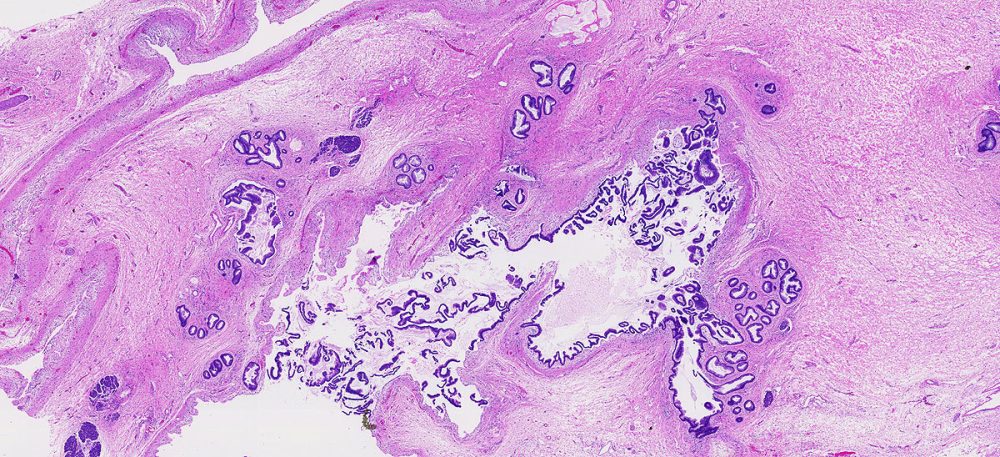

A fluid filled sac. Some tumors of the pancreas, including the serous cystadenomas and intraductal papillary mucinous neoplasms, form cysts. Cysts have a distinct appearance in CT scans. They are important to recognize because the treatment of cystic tumors can differ from that for solid tumors.

A benign (non-cancerous) tumor made up of cells that form glands (collections of cells surrounding an empty space).

The form of cancer that most people are talking about when they refer to "cancer of the pancreas." These tumors account for 75% of all pancreas cancers.

Microscopically, adenocarcinomas form glands. These tumors can grow large enough to invade nerves which can cause back pain. They also frequently spread (metastasize) to the liver or lymph nodes. If this happens the tumor may be considered unresectable.